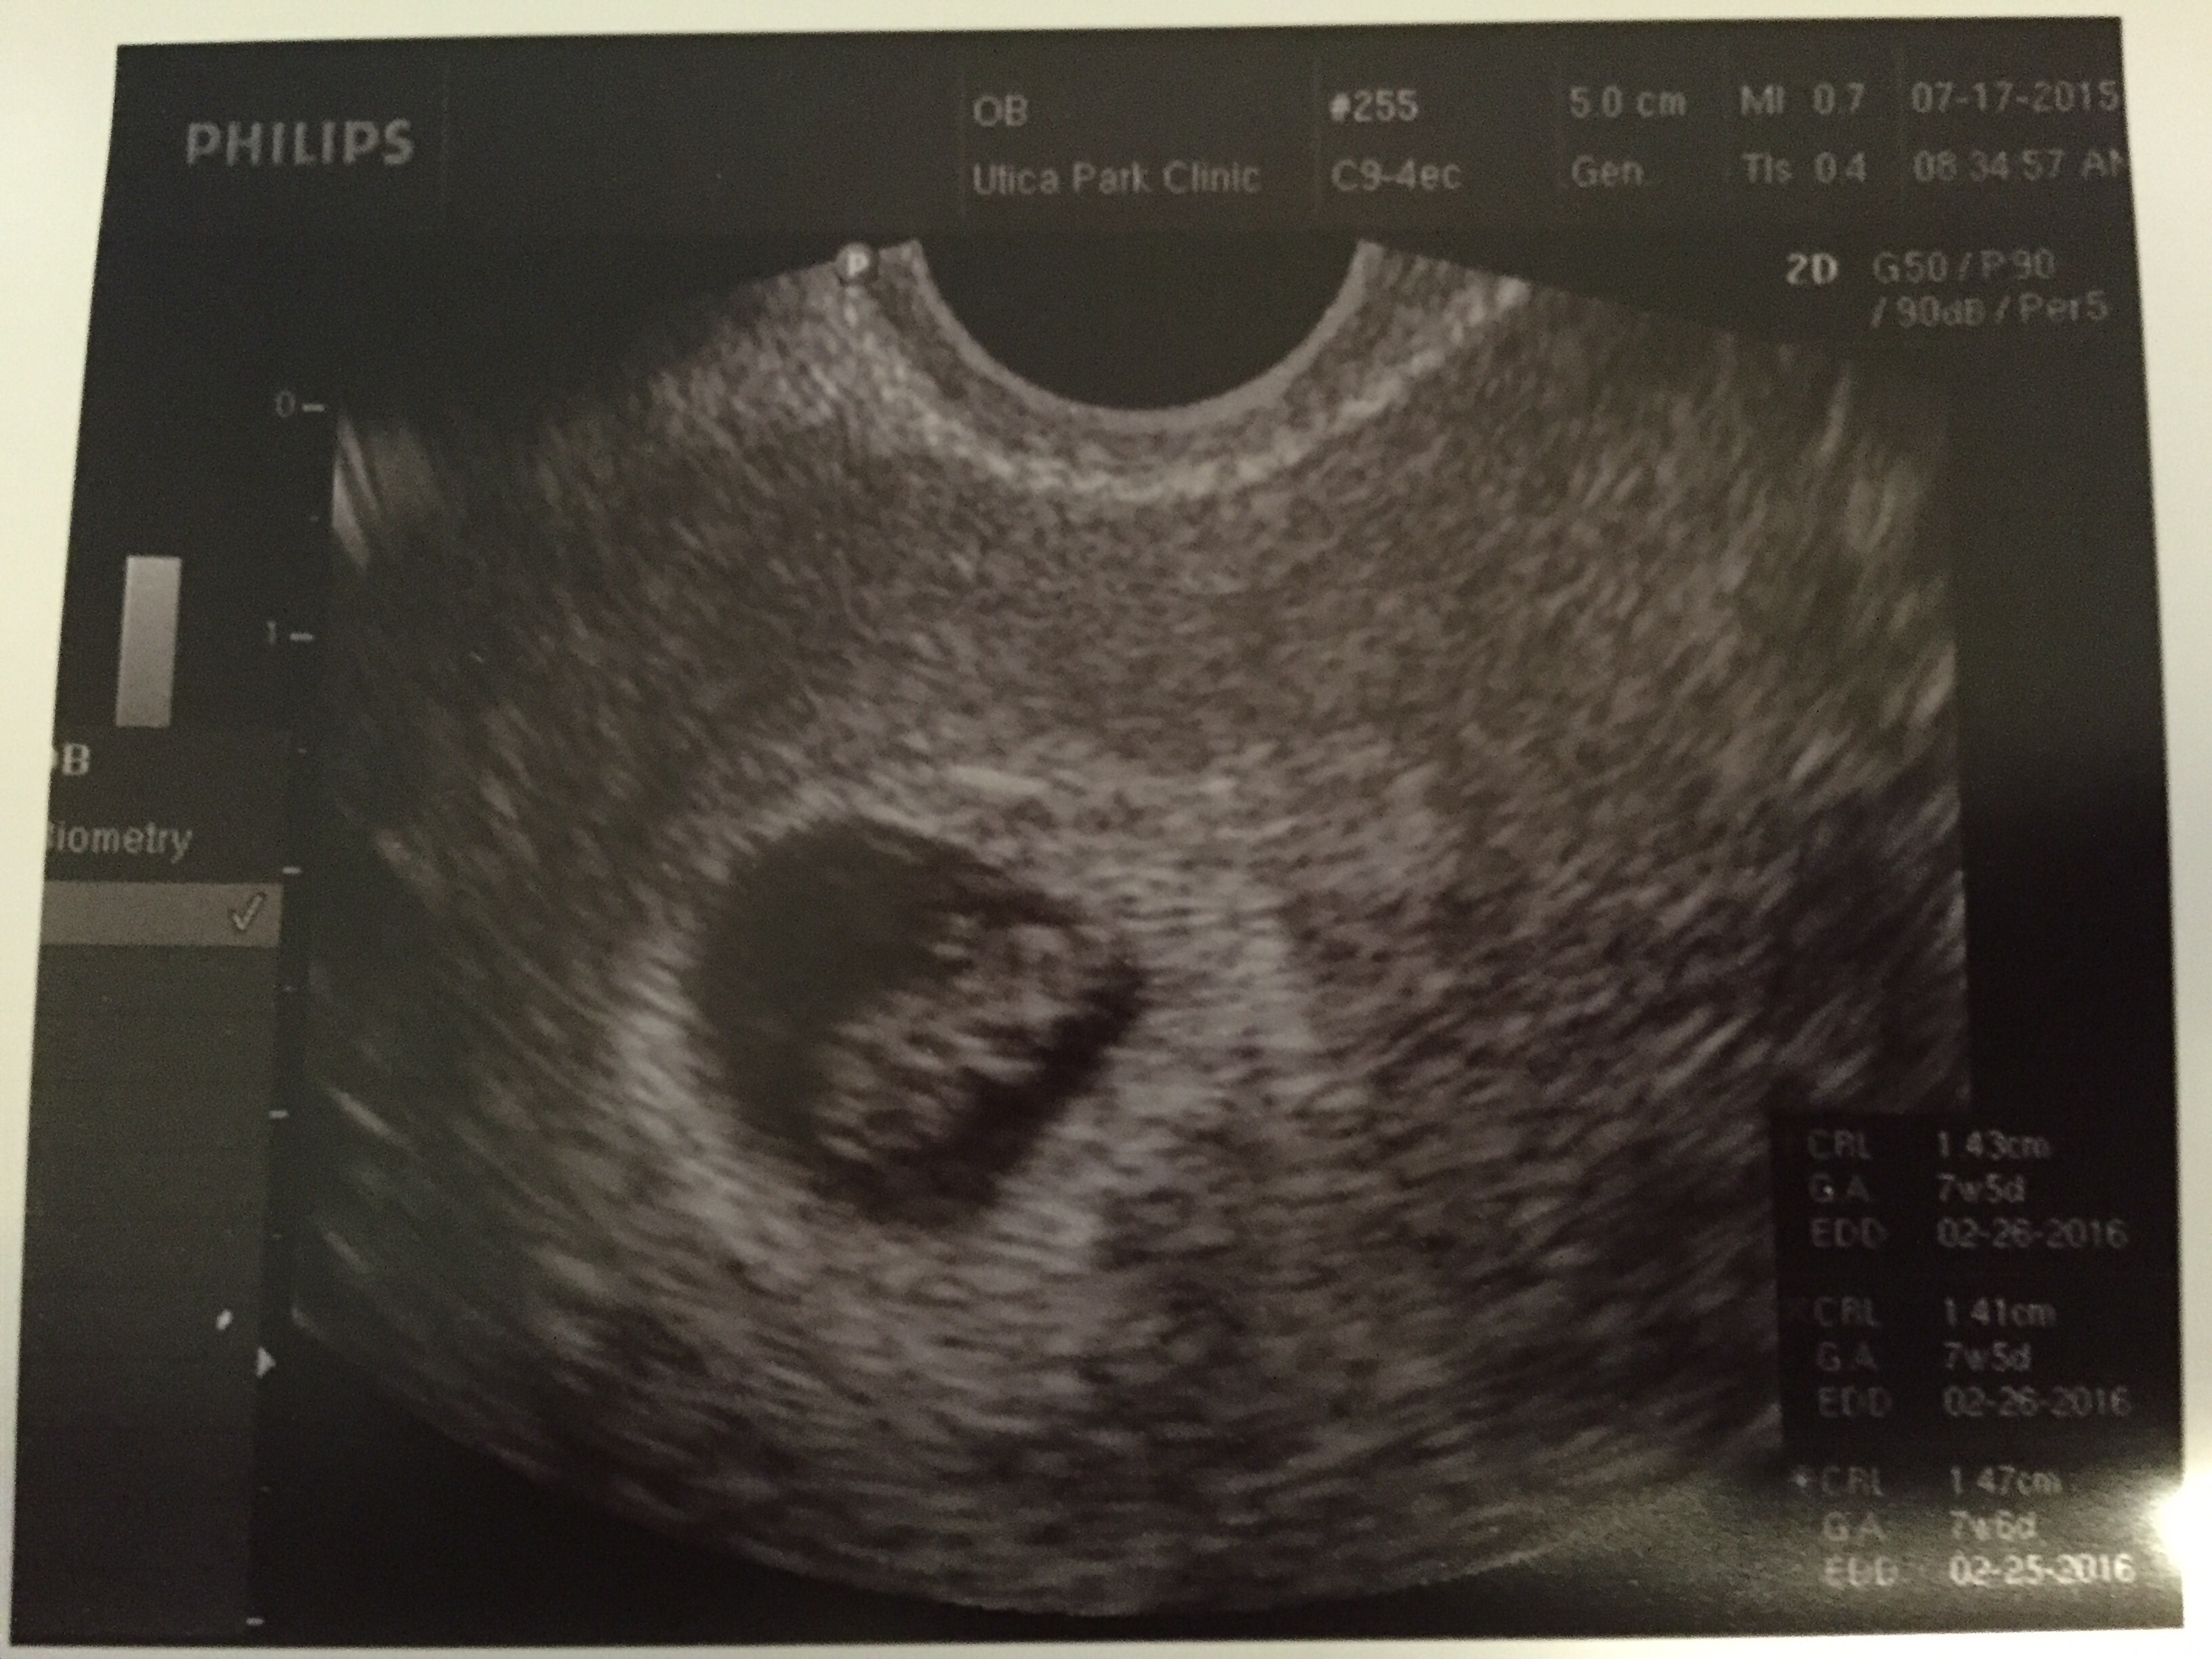

This is mine and my husband's first baby. One year ago on April 29th I had gastric bypass and lost 100 lbs which I believe helped us be able to have a baby. We are currently at 10 weeks and our due date it Feb 14th. It is kind of strange because I was born 3 days before my grandma's birthday and our due date is the Feb 14th and my grandpa's birthday is the 6th. (My great grandpa's birthday is Feb 15th)